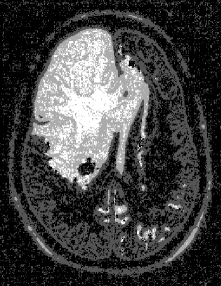

Figure 6a555From the Iowa Neuroradiology Library (http://www.uiowa.edu/c064s01/index.html). Used with permission. shows an MRI image of a brain with a tumor in the upper left quadrant. The segmented image using the direct Potts segmentation method with Q=64𝑄64Q=64 and st=31.5subscript𝑠𝑡31.5s_{t}=31.5 is shown in Fig. 6b. After filtering, we obtain the the image in Fig. 6c. Here, the white regions may be interpreted as possible tumorous tissue, light gray corresponds to matter at the periphery of the tumor, dark gray represents cerebrum, and black is other brain matter. Automated screening for tumors may be performed by finding white regions of significant size. Although, the four-level histogram method (Fig. 6d) also identifies a similar tumor region, the cerebrum is not distinguished from other brain matter. The affect of the chosen value for Q𝑄Q is demonstrated in Fig. 7. Larger values of Q𝑄Q result in more of the image being categorized as textured (represented as light and dark gray). Finally, acoustic seafloor images may be analyzed in real-time with the direct Potts segmentation method as demonstrated in Fig. 8. Here sand ripples are identified (in green) as a grainy texture and is separated from the remainder of the image. Rapid seafloor characterization enables effective mine hunting/avoidance operations bentrem06 ; bentrem02 ; bentrem08 , by indicating where seafloor mines are likely to be buried (mud), partially buried (sand), or unburied (rock).

Refer to caption

Figure 6: MRI of a tumorous brain at upper left (a). A tumor is seen as the bright spot in the upper left region of the MRI. This image is from the Iowa Neuroradiology Library. Image at upper right (b) is the direct Potts segmentation with Q=64𝑄64Q=64, st=31.5subscript𝑠𝑡31.5s_{t}=31.5. Lower left (c) is the direct Potts segmentation that has been despeckled. The clearly visible white segment identifies the tumor. A tumor is clearly visible as the bright spot in the upper left region. The periphery of the tumor is shown in light gray, while cerebrum is represented as dark gray. Other brain matter is shown in black. For comparison, lower right (d) is the despeckled four-level histogram segmentation, which identifies the tumor region, but cannot distinguish cerebrum from other brain matter.